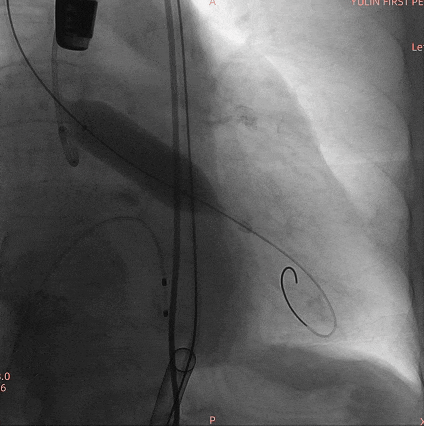

手术过程

通过术前精准评估,患者在全麻下行TAVR手术,DSA和食道超声双重引导,通过右侧股动脉建立工作路径,沿加硬导丝送入19mm*40mm球囊预扩张主动脉瓣,预扩时双侧冠脉显影良好。退出预扩张球囊后,利用可调弯输送器送入23#RENATUS瓣膜至升主动脉,猪尾巴导管再次造影确认位置。将23#RENATUS瓣膜顺利跨瓣,精准定位,4ATM精确释放,退出输送系统再次行主动脉根部造影,示瓣膜膨胀充分,无瓣口反流,无瓣周漏,冠脉血流正常,再次测主动脉根部压力及左心室压力,术后即刻平均跨瓣压差降至3.33mmHg,超声示术后峰值流速降至0.91m/s。瓣膜释放位置理想、形态及功能良好,瓣叶启闭良好,无外周血管损伤。

主动脉根部造影

19mm球囊预扩

瓣膜定位

23#Renatus瓣膜释放中再次造影定位

释放后造影示瓣膜位置理想,形态良好